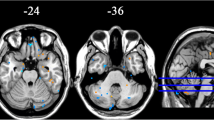

Our exploratory findings showed that, compared with NCs, the PD baseline acquisitions had decreased ReHo in the SMA, the bilateral precentral gyrus, and the bilateral postcentral gyrus [sensorimotor cortex (SMC)], and increased ReHo in the right superior temporal gyrus and right hippocampus (Fig. 2; Table 2). The VBM analysis did not reveal any differences in GM volume and density between the NC and baseline PD acquisitions.

Longitudinal Results

Compared with the PD baseline results, the PD follow-up images showed significantly decreased ReHo in the SMC, DMN (bilateral precuneus, bilateral angular gyrus, bilateral parietal lobule, bilateral middle frontal lobule, and anterior cingulate cortex), and left cerebellum, and increased ReHo in the SMA, bilateral temporal gyrus, and bilateral hippocampus (Fig. 3A, B; Table 2). A similar pattern was also found when the PD baseline images were compared with those from the NC group. Moreover, there was a correlation between the rate of ReHo change in the left cerebellum and the rate of UPDRS-III score change (R = 0.41; P < 0.05; Fig. 4) over the 2 years. The VBM analysis revealed no significant differences in GM volume and density between the follow-up and baseline sessions.

As far as we are aware, this is the first longitudinal research using ReHo to explore changes in local spontaneous brain activity in PD patients. We demonstrated that compared with NCs, the PD baseline images showed a tendency for decreased ReHo in the SMC and increased ReHo in the SMA, right superior temporal gyrus, and right hippocampus. However, the follow-up analysis of the PD patients demonstrated significantly decreased ReHo in the SMC, DMN, and left cerebellum, while ReHo in the SMA, bilateral temporal gyrus, and hippocampus significantly increased. Moreover, the correlation analysis showed that the rates of ReHo change in the left cerebellum were significantly correlated with the rates of change in the UPDRS-III scores.